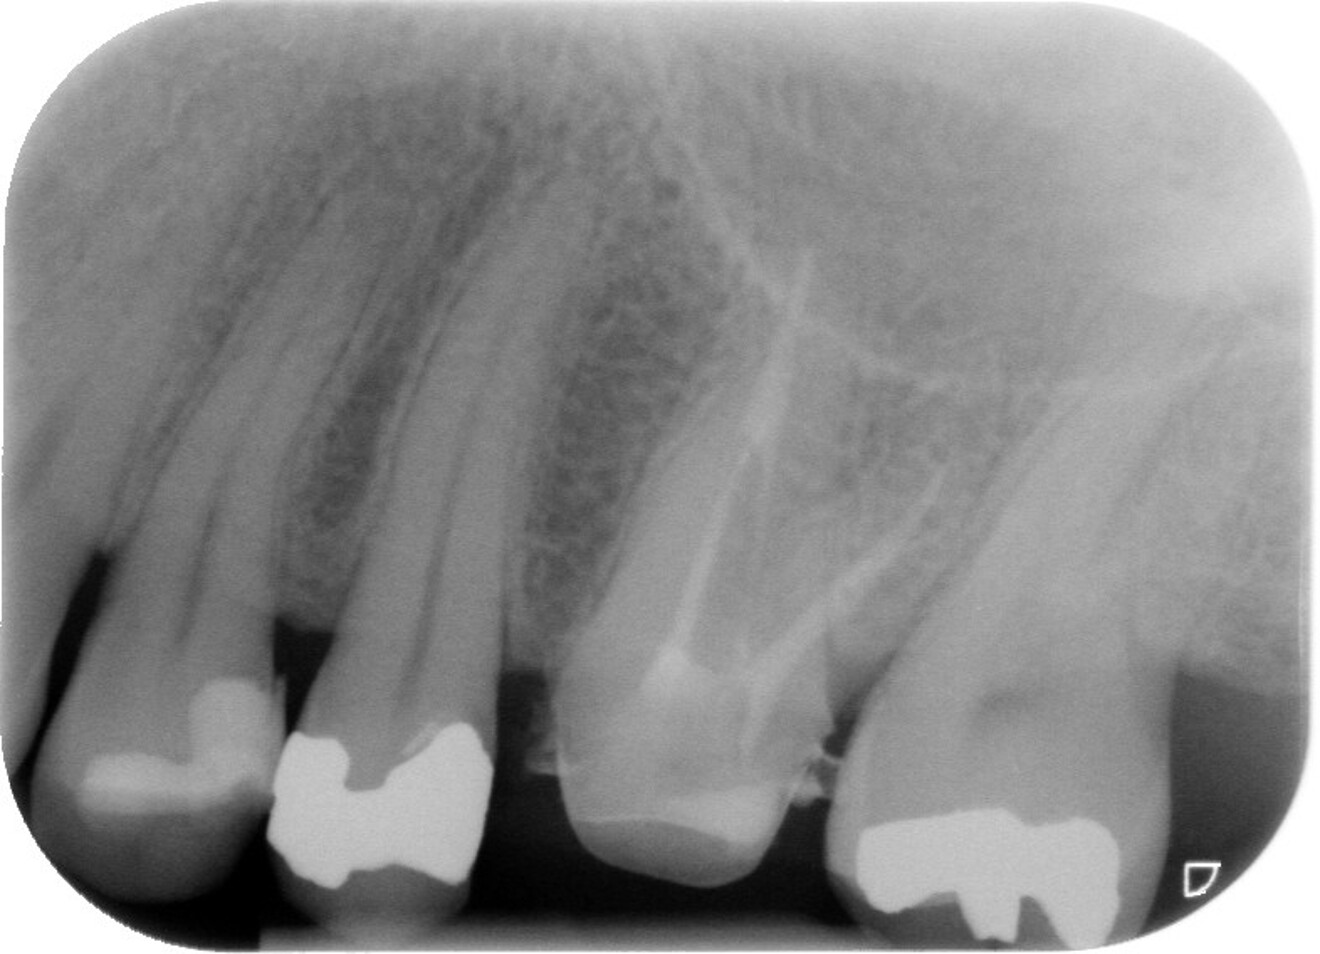

Fig. 1 : Radiographie préopératoire montrant la présence d’une reconstitution corono-radiculaire coulée, ancrée dans les trois canaux.

D’un point de vue pratique, la première étape consiste à réduire les dimensions du tenon s’il occupe une grande partie de la structure coronaire, de préférence en lui donnant une forme cylindrique similaire à celle d’un tenon préfabriqué. De même, une reconstitution corono-radiculaire coulée ancrée dans plusieurs canaux doit d’abord être sectionnée jusqu’au niveau du plancher de la cavité pulpaire, afin de la traiter comme un ensemble de tenons unitaires, ce qui diminue le degré de rétention global du système. La réduction du tenon doit être effectuée avec des fraises en carbure spécialement conçues pour découper le métal, sous une irrigation abondante. Les évaluations cliniques et radiographies préliminaires sont essentielles pour planifier l’angle de coupe. La procédure doit être fréquemment vérifiée et, si nécessaire, il convient d’effectuer des contrôles radiographiques avant qu’une quantité excessive de dentine ne soit sacrifiée (Figs. 1–3).